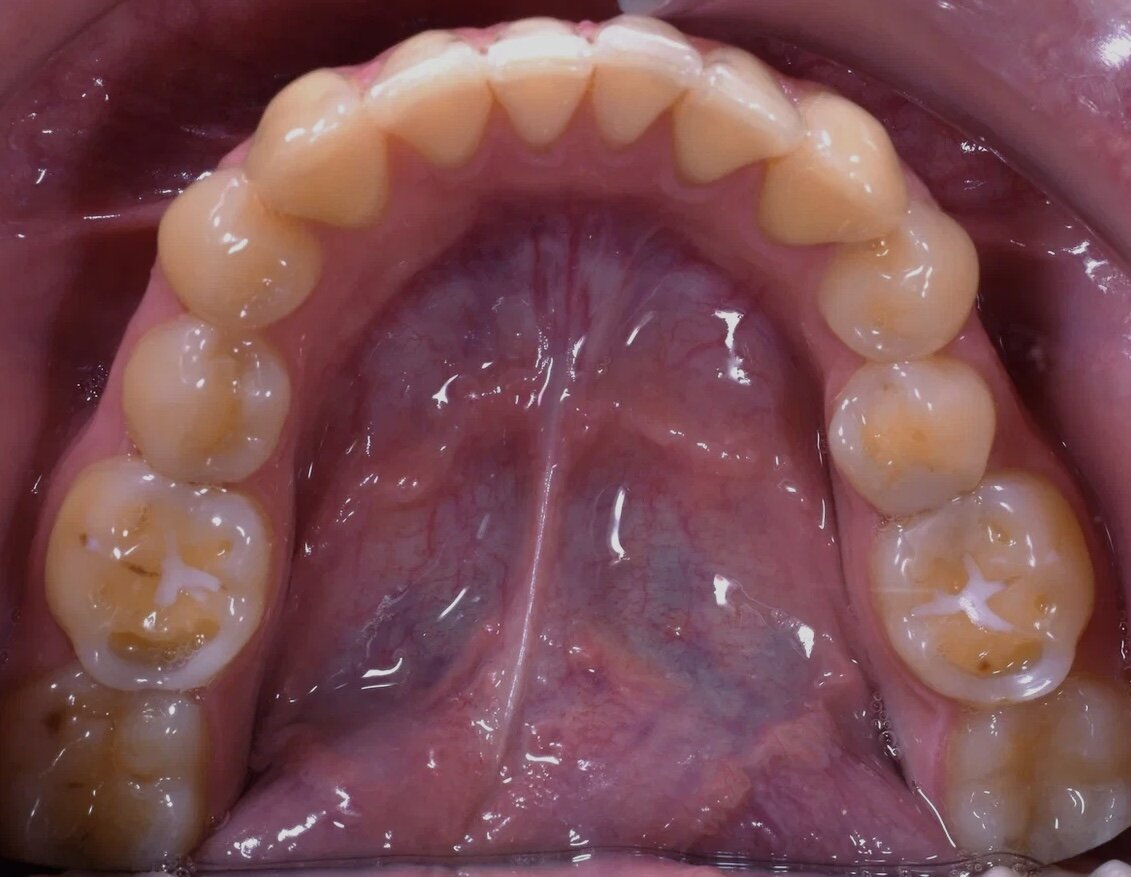

Пациентка обратилась с жалобами на сильную стираемость и чувствительность зубов. Также, был выявлен неправильный прикус и сильный спазм жевательных мышц, который доставлял ей дискомфорт.

Итак, на этой фотографии мы видим ярковыраженную стираемость зубов.

Проведя ряд диагностик, мы определили следующие проблемы:

• Неправильный прикус

• Бруксизм

• Спазм мышц

• Стираемость зубов

• Расхождение центральных линий

• Чувствительных зубов

Далее мы удалили 8ые зубы и тем самым, создали место для правильного расположения зубов. Этап удаления 8ых зубов проходит 90% пациентов в нашей клинике, так как чаще всего зубы «мудрости» препятствуют правильному движению всего зубного ряда.

Далее мы зафиксировали пациентке брекеты и установили 1 мини-винт, который задавал ход движения зубов для восстановления центральной линии на верхней челюсти.